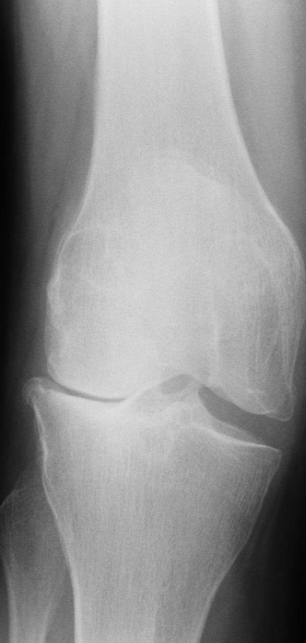

A. Give ONE radiological sign for an abnormal

wrist/knee.

B. What is the most likely diagnosis in the given image? Rickets

- Growth plate is widened

- Metaphysical margin is cupped and irregular

Imaging modality Lateral compartment osteoarthritis of the knee X-ray right knee (AP view)

Findings Osteophytes - bone spurs // Subchondral Sclerosis

Diagnosis Osteoarthritis